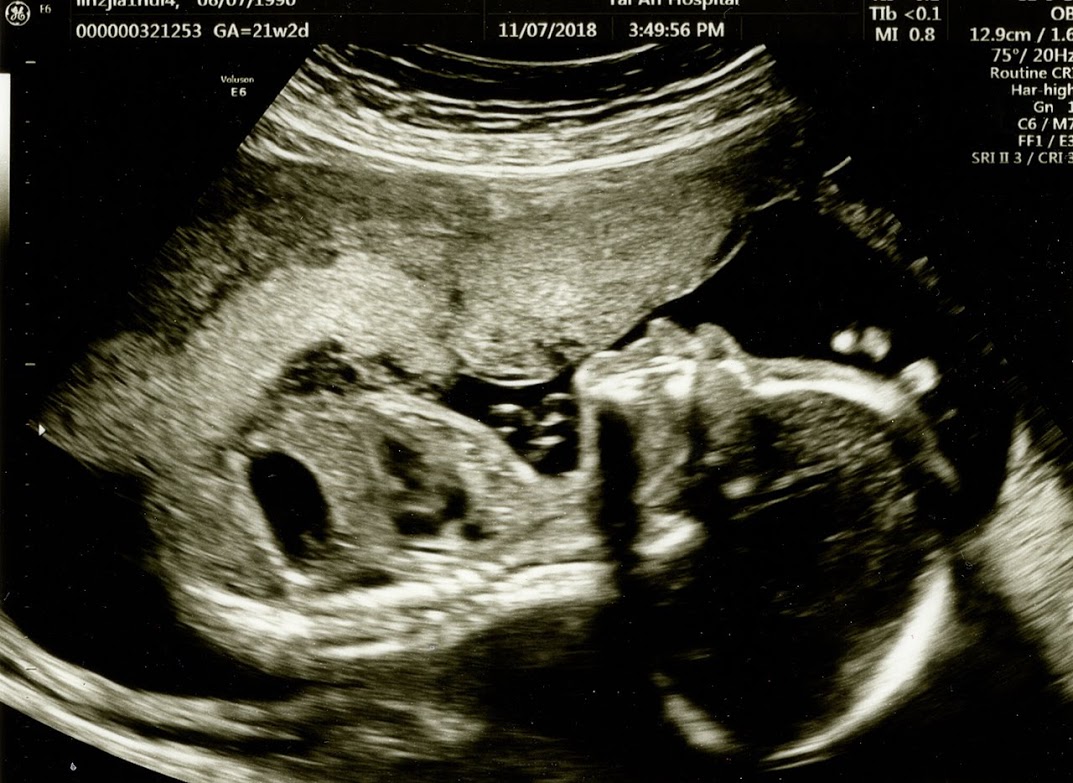

莫約等待了半小時,終於輪到我進去第二次的檢驗了! 這次寶寶的確乖了一點,沒讓媽媽被敲敲打打,但程序都結束後,張慧怡醫師緊接著進行陰道超音波檢驗,她說要看一下子宮頸的長度?? 雖然這過程沒有很久,也不會感到疼痛或不舒服,但張慧怡醫師說我整個人太緊張啦!!!! 其實我害怕的是….是怕會放屁?

這次的高層次超音波,不僅獲得一份有點厚度的報告,也拿到了許多寶寶的超音波照片,就拿幾張來分享啦!!!